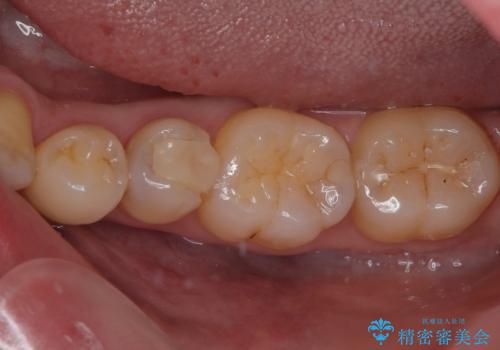

左下にフロスを通すと引っかかる オールセラミッククラウン

担当医 有澤哲郎